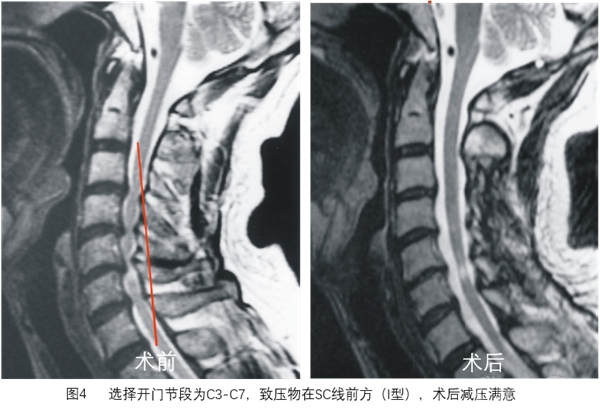

SC线同时反映颈椎管曲度、脊髓曲度与致压物的关系,根据SC线及其分型能更好地预测颈椎开门椎管成形术后脊髓减压的效果(图3~图8)。

在MR T2像脊髓矢状位上画线,具体方法见图1。根据SC线与前方致压物关系可分为3型:I型为致压物在SC线前方,II型为致压物与SC接触,III型为致压物超过SC线(图2)。

选择开门节段后,划出SC线,分型为I型开门术后减压满意,II型大部分可获得减压,III型减压不满意。